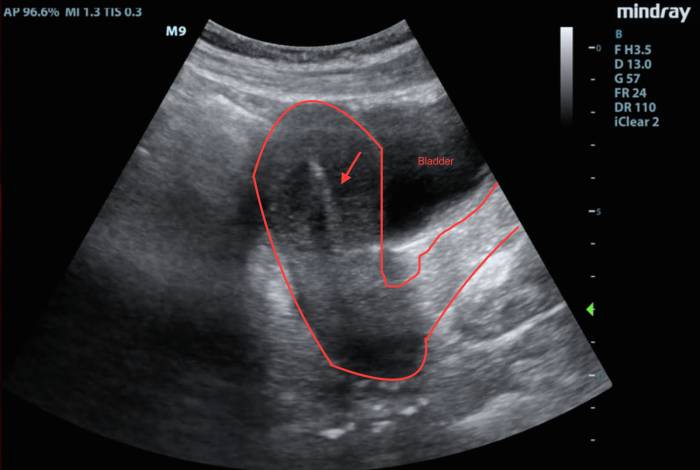

- УЗИ органов малого таза;

Поскольку загиб матки является анатомической особенностью, после установки контрацептива врач советует пациентке проверить правильность расположения спирали с помощью УЗИ.